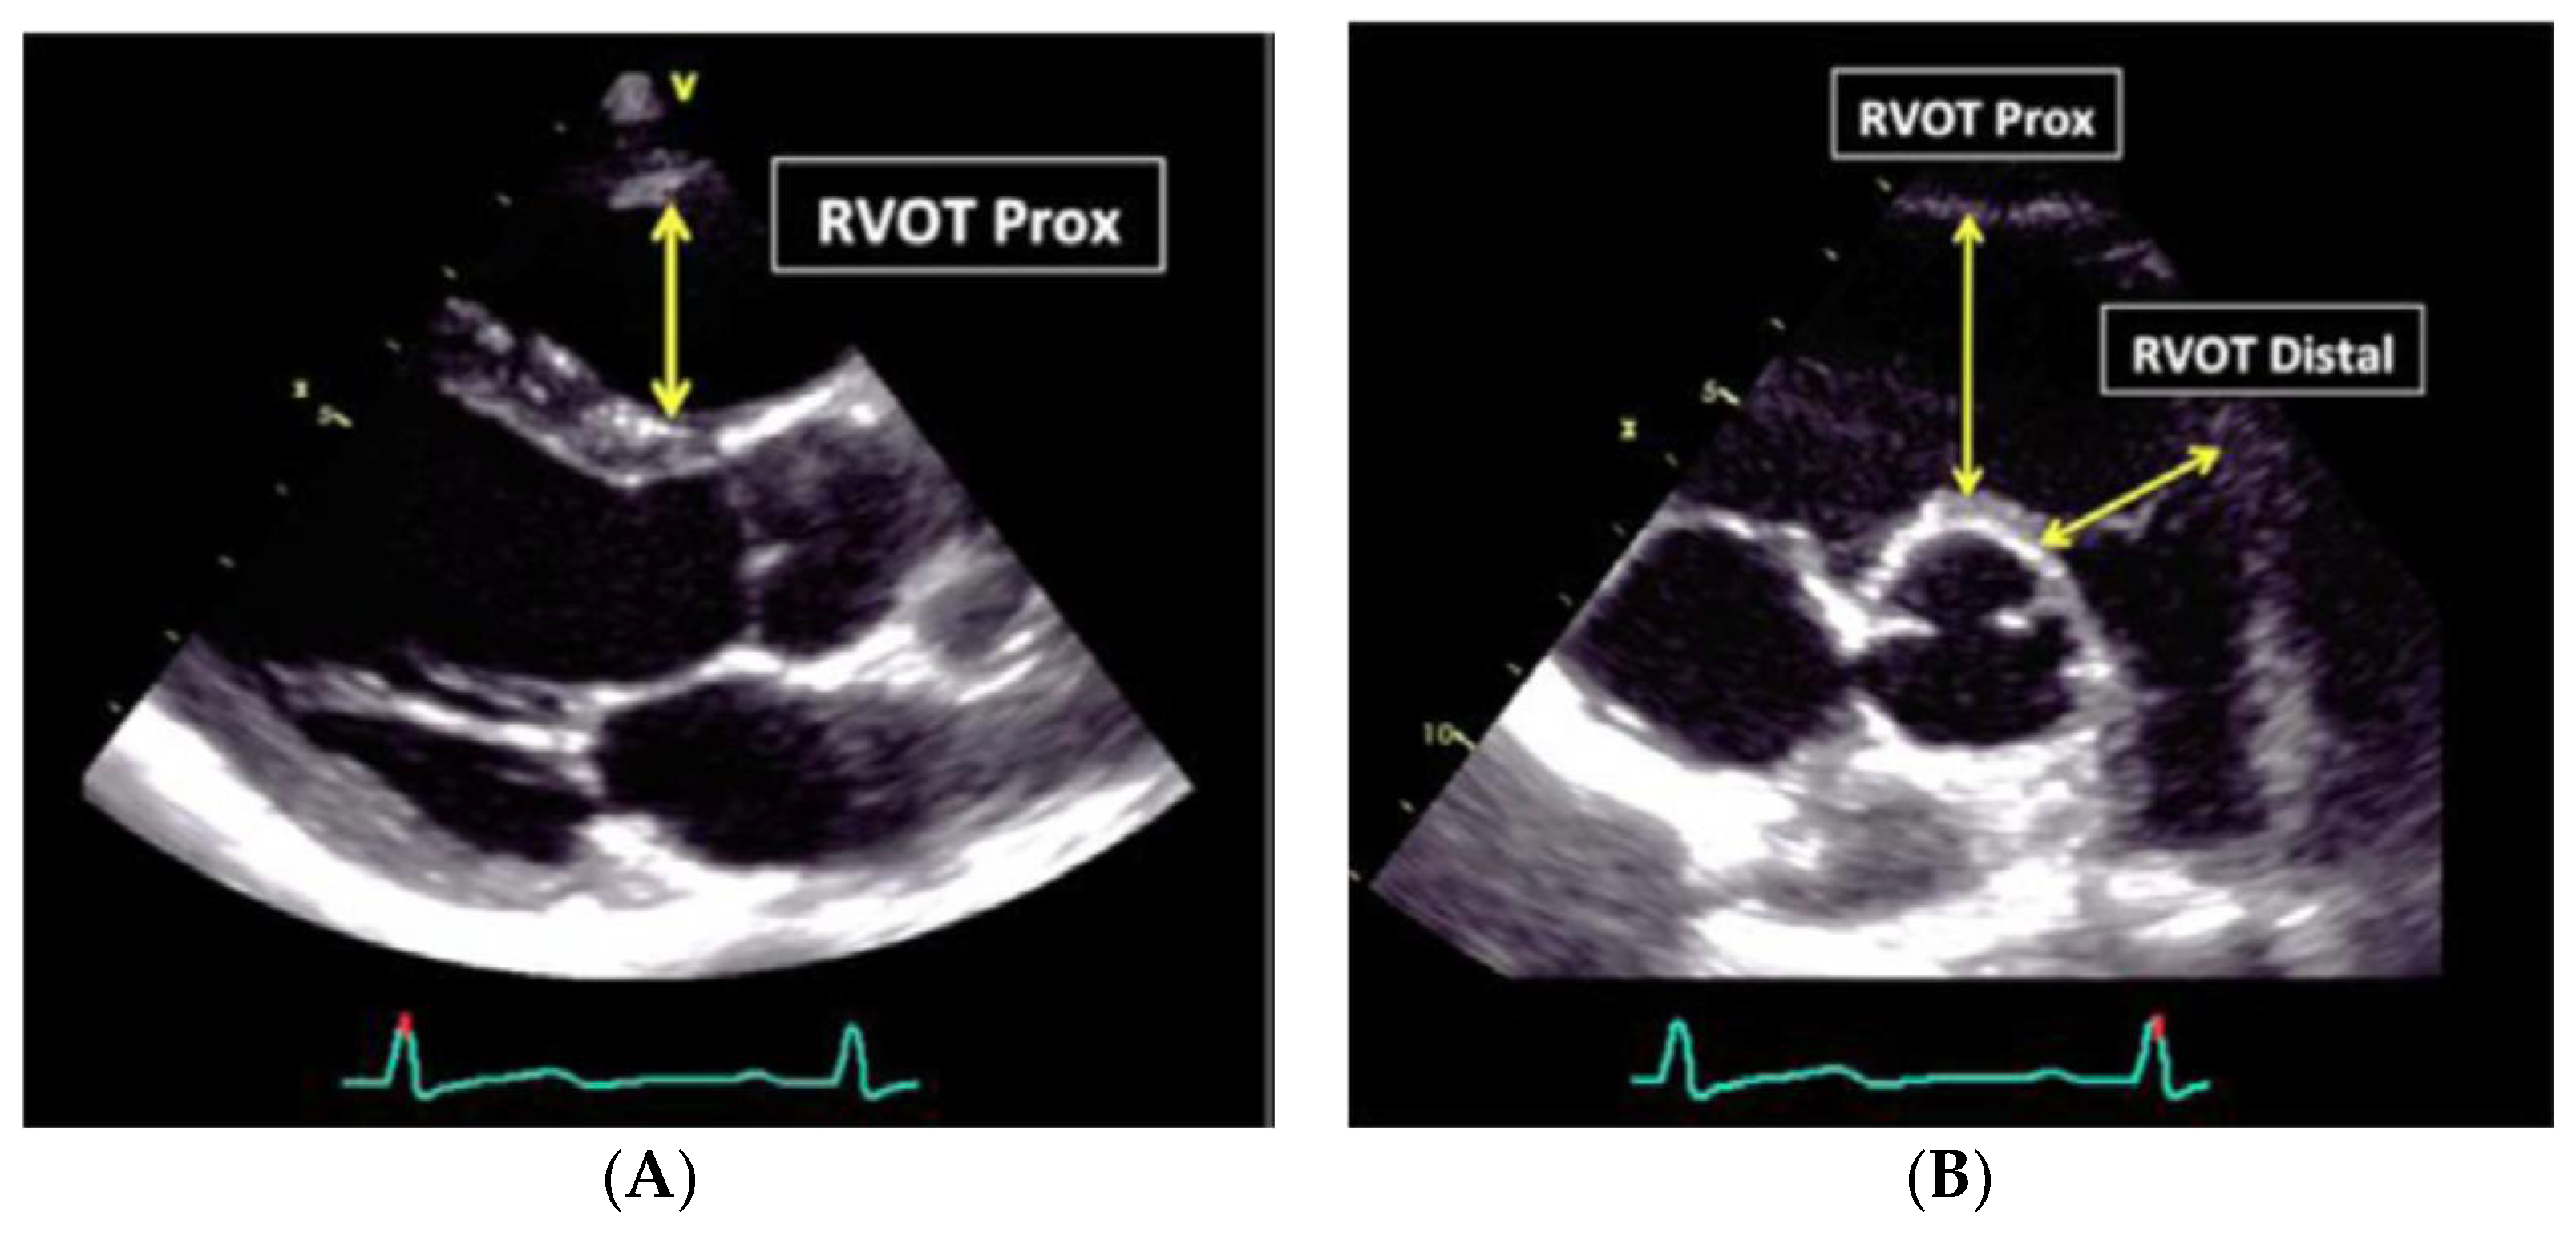

7. Echocardiographic Assessment

- RV outflow tract diameter (long axis) >32 mm, or

- RV outflow tract diameter (short axis) >36 mm, or

- RV shortening fraction <33%

| Parameter | Pathological Values | Normal Range |

|---|---|---|

| RV Area Change | Fractional Area Change <33 | >40% |

| RVOT PLAX diameter | >33 mm | 20–30 mm |

| RVOT prox diameter | >36 mm | 21–35 mm |